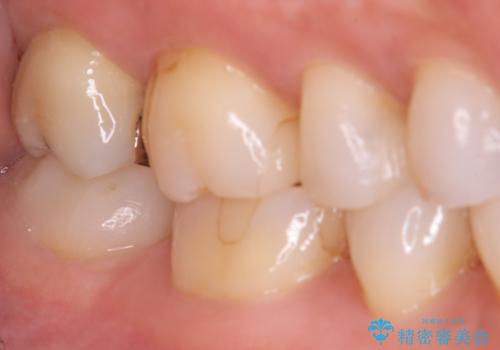

- 昔入れたメタルインレーの下にむし歯が再発したため治療を行った患者様です。

メタルインレーは汚れが付着しやすく、適合も悪いことがあるため、むし歯が再発しやすかったと思われます。

フロスなどの日常の清掃はもちろん不可欠ですが、メタルインレーより汚れが付着しずらいセラミックインレーにて今回は治療を行いました。